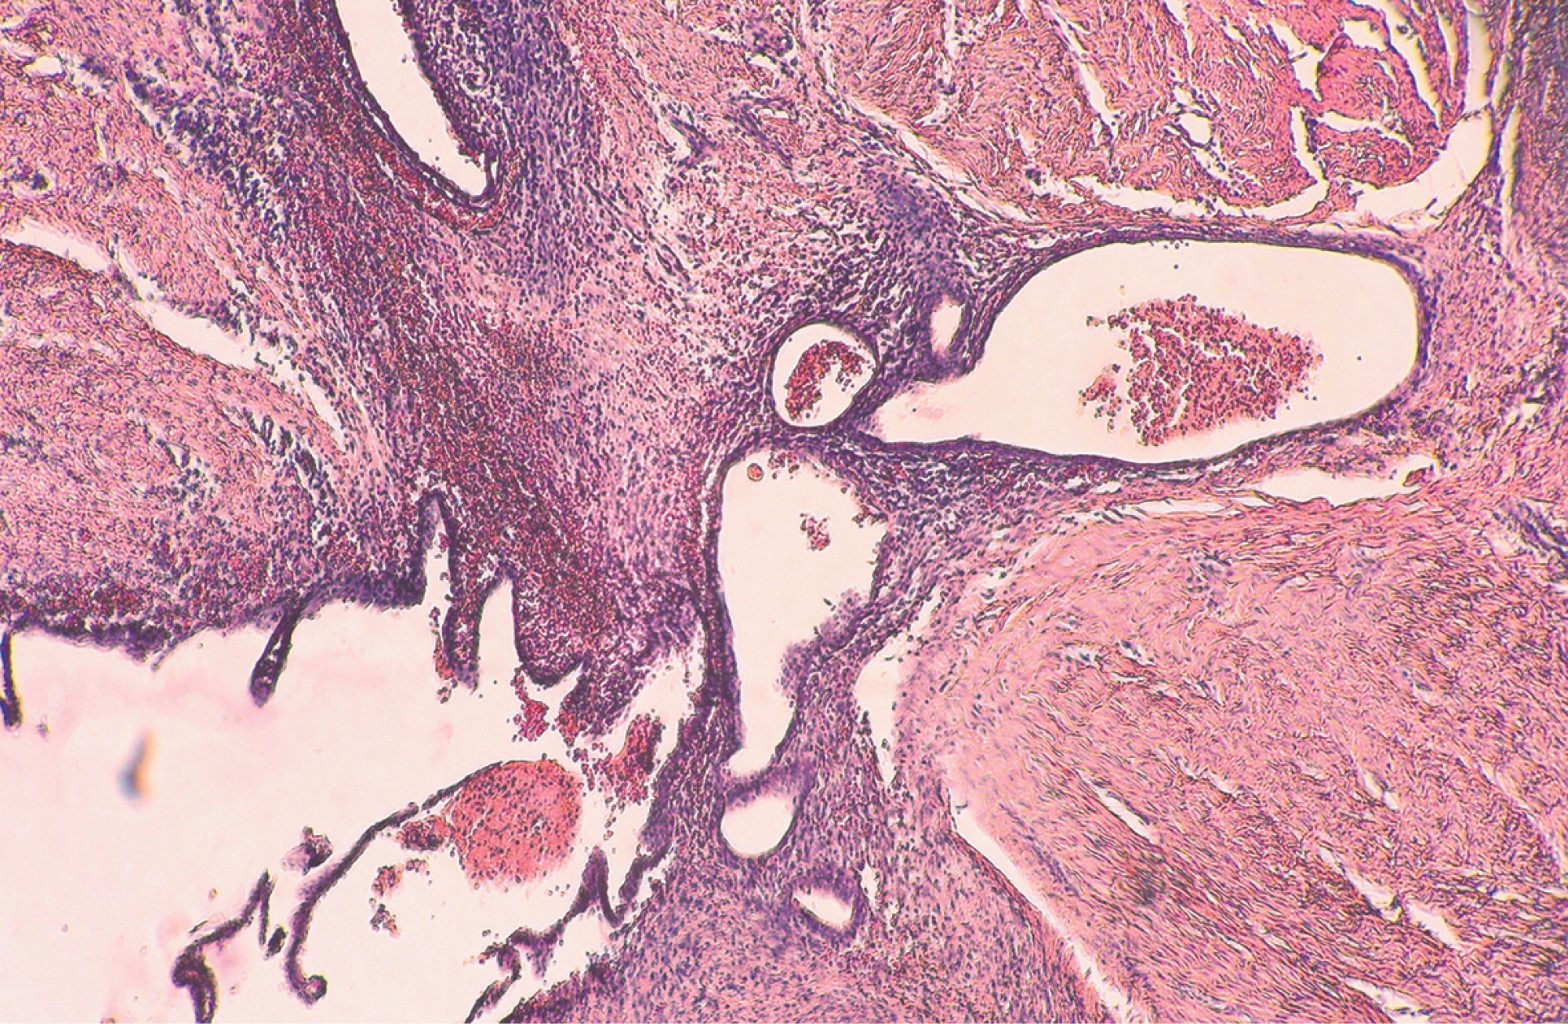

El estudio histopatológico de las lesiones confirma el diagnóstico. En éste se observan glándulas y estroma endometrial entre los haces de tejido conectivo. Las glándulas tubulares se aprecian parcialmente ensanchadas y recubiertas de epitelio columnar. El estroma celular muestra áreas de edema, con algunos linfocitos y hemosiderófagos.4,10

Con la impresión diagnóstica de un probable lipoma versus endometrioma se envía al servicio de cirugía dermatológica de la unidad para valoración, en donde se le programa para extirpación de la lesión. Durante el procedimiento se realiza disección hasta llegar a tejido celular subcutáneo profundo y fascia abdominal. Al llegar a este plano anatómico, se observa una masa amorfa fibrosa en la cual no se distinguen bordes (Figura 2). Se envía la pieza extraída al servicio de dermatopatología. El resultado del estudio histopatológico mostró tejido conjuntivo con amplias zonas de fibrosis e incremento en el número de fibroblastos. Entre las fibras de colágeno se aprecian numerosas cavidades de tipo glandular, todas ellas revestidas por una delgada pared de células secretoras de tipo apócrino. Se observan restos celulares, eritrocitos y fibrina en el interior de las cavidades, así como moderada reacción inflamatoria en el estroma circundante (Figuras 3 y 4). El diagnóstico histopatológico fue sugestivo de endometriosis.

Figura 3

Figura 4